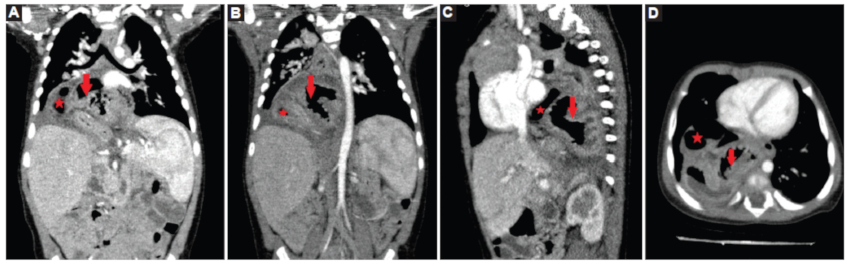

Reconsultó tras 20 días por reaparición de vómitos hemáticos y pérdida ponderal. En la exploración física destacó una hipoventilación en base pulmonar derecha, sin signos de dificultad respiratoria y afebril, con analítica sanguínea anodina. Se realizó una radiografía de tórax, objetivando una imagen en base pulmonar derecha compatible con hernia diafragmática (Fig. 1), hallazgo que permitió la realización de pruebas confirmatorias (Figs. 2 y 3) y un manejo precoz y adecuado del caso.

Se realizó intervención quirúrgica laparoscópica objetivando gran hernia a través de hiato esofágico que incluía colon transverso, estómago completo incluido el píloro y primera porción duodenal en situación invertida, sin signos de estrangulación. Se realizó reducción, resección parcial del saco herniario, cierre de los pilares, fijación de esófago a diafragma y funduplicatura de Nissen, previniendo la aparición de reflujo gastroesofágico posquirúrgico, presentando evolución posterior satisfactoria sin complicaciones.

La confirmación diagnóstica debe realizarse con un estudio radiológico esófago-gastro-duodenal con contraste. La realización de tomografía computada (TC) habitualmente debe reservarse para casos donde existan dudas diagnósticas o para precisar la posición anatómica3.